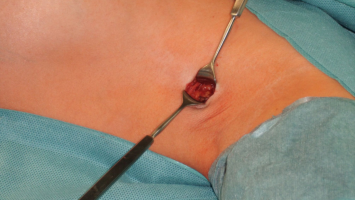

Sentinel-Lymphknoten-Biopsie genügt bei frühen Zervixkarzinomen

Zeigen Wächterlymphknoten bei frühen Zervixkarzinomen keinen Befall, ist auch keine pelvine Lymphadenektomie nötig. Nach drei Jahren war die krebsspezifische Sterberate in einer Studie nicht höher, die Komplikationsrate aber geringer als nach der Lymphadenektomie.